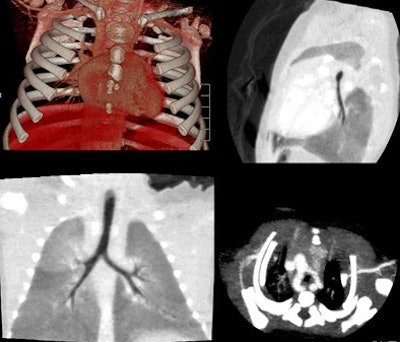

| Vascular ring and hypothesis of tracheal stenosis. Images at 320-detector-row CT. |